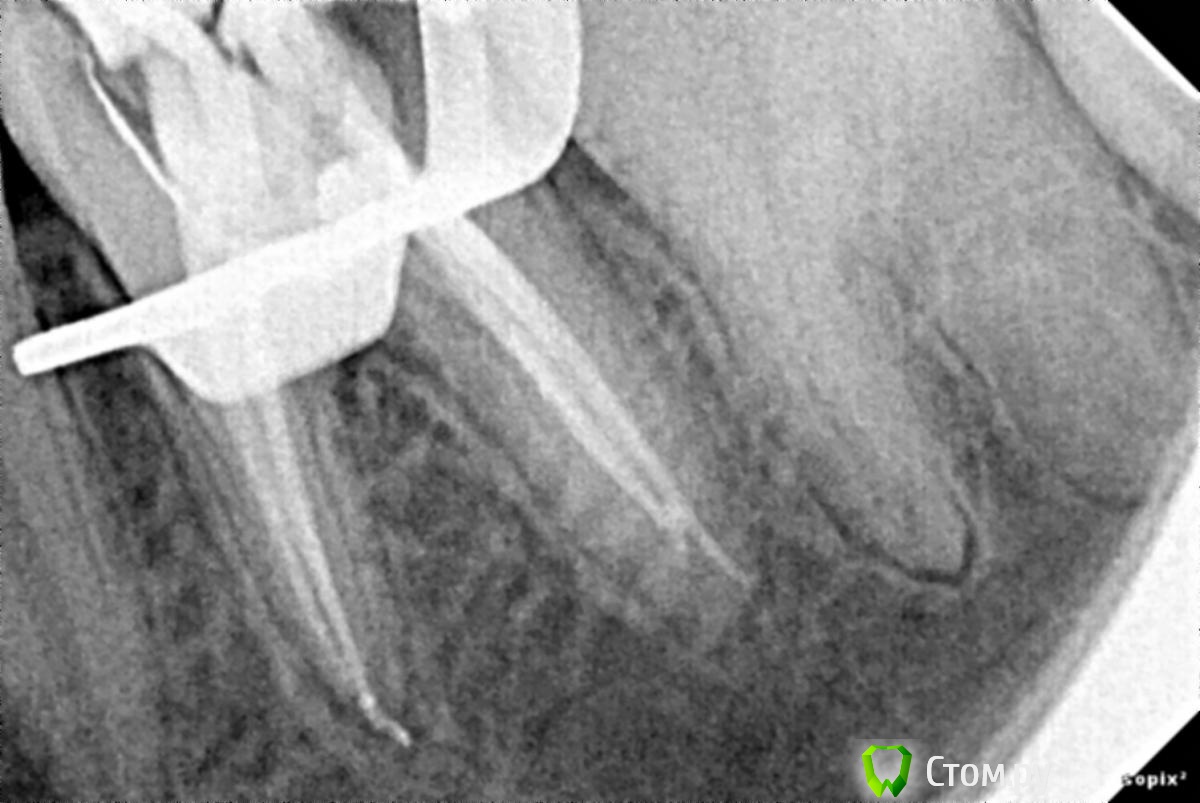

Arseniy Опубликовано 10 декабря, 2013 Поделиться Опубликовано 10 декабря, 2013 Всем доброго время суток. Хотел поделиться своей первой эндодонтией на, так сказать, живых людях. До этого практиковался на эндобоксах и мертвых зубах. Учусь на пятом курсе. Обработка каналов происходила ручными файлами + ручные pro taper. Ирригация 3,25% гипохлоритом натрия, ЭндоЖи №1.Обтурация термофилами 25 + AH plus.Использовал RC преп. Хотелось бы послушать критику коллег 4 Ссылка на комментарий

M@estro Опубликовано 10 декабря, 2013 Поделиться Опубликовано 10 декабря, 2013 (изменено) часто на Rg видна пломбировка ответвлений от основного канала. Пломбирует более герметично. http://s017.radikal.ru/i435/1312/7b/ef857d8e1cf3.jpg Чем канал обтурирован ? Хотел бы посмотреть,как его обтурировать термафилом. Чем бор вас не устраивает? Да отлично, "пилите ,Шура,пилите ! " (с) . Нам больше достанется. Изменено 10 декабря, 2013 пользователем M@estro Ссылка на комментарий

Каплан Опубликовано 10 декабря, 2013 Поделиться Опубликовано 10 декабря, 2013 За коффердам плюс и похвалы. За темафил, ерзание бором по дну, и маленький апикальный размер- атата. Для первого эндо- у вас огромный потенциал. Где делали, если не секрет? Кафедра или частная клиника ? Ссылка на комментарий

АнтонТЛТ Опубликовано 10 декабря, 2013 Поделиться Опубликовано 10 декабря, 2013 Сравнивал снимки латералки и термофилов. При хорошей ирригации и озвучивании каналов при пломбировке термофилом часто на Rg видна пломбировка ответвлений от основного канала. Пломбирует более герметично. На мой взгляд лучше всего вертикалка, потом латералка, потом софт-кор с термафилом Минус гутты на носителе это "эффект шампура" (на снимке может быть все хорошо, но на самом деле в апексе только носитель без гутты).Второй минус это препарирование под вкв, носитель иногда может мешать.Третий минус это более сложная распломбировка в случае обострения.На счет очищения пульпарной камеры, лучше аирфлоу + экскаватор.Ну и рс-преп лучше не использовать, из-за своей густоты он создает повышенное напряжение на файлах (могут сломаться). Просто хлорки хватит за глаза. 2 Ссылка на комментарий

Kivilgar Опубликовано 11 декабря, 2013 Поделиться Опубликовано 11 декабря, 2013 Считаю, что в разы удобнее, чем латералить,и качественнее. Да, возможно удобней и быстрее, латеральная однозначно дольше.Не качественней, почему вы так считаете? Неоднократно ученые мужи проверяли, нет подтвержденных данных превосходства ни одного современного метода обтурации над другим. Вид красивой картинки не показатель. Сравнивал снимки латералки и термофилов. При хорошей ирригации и озвучивании каналов при пломбировке термофилом часто на Rg видна пломбировка ответвлений от основного канала. Пломбирует более герметично. Не герметичней, а зачастую хуже чем латералка. Откуда у вас такая уверенность, на чем основана? Соглашусь, что не всегда термофил подойдет, но в моем случае ИМХО он предпочтительнее.На чем основано это ваше заключение? Ссылка на комментарий

Мартовский Опубликовано 11 декабря, 2013 Поделиться Опубликовано 11 декабря, 2013 Мне термофил понравился. Я их не отскребаю, а высверливаю шариком алмазным. Считаю, что в разы удобнее, чем латералить, и качественнее. Ух сколько я натермафилил за восемь лет… Метод хороший, но все же это фастфуд, типо быстрая обтурация горячей гутаперкой. С этим методом надо либо работать постоянно, либо вообще не браться, слишком много нюансов. Латералке явно уступает в прогнозировании - брызнет-не брызнет, ну и как сказали, гутта может с носителя слазить, а картинка на рвг будет красивая.Носитель лучше срезать термопрепом, потом наливаете в полость спирт, и ватным шариком соскребаете остатки. Что не снялось, то убираем экскаватором. Ссылка на комментарий